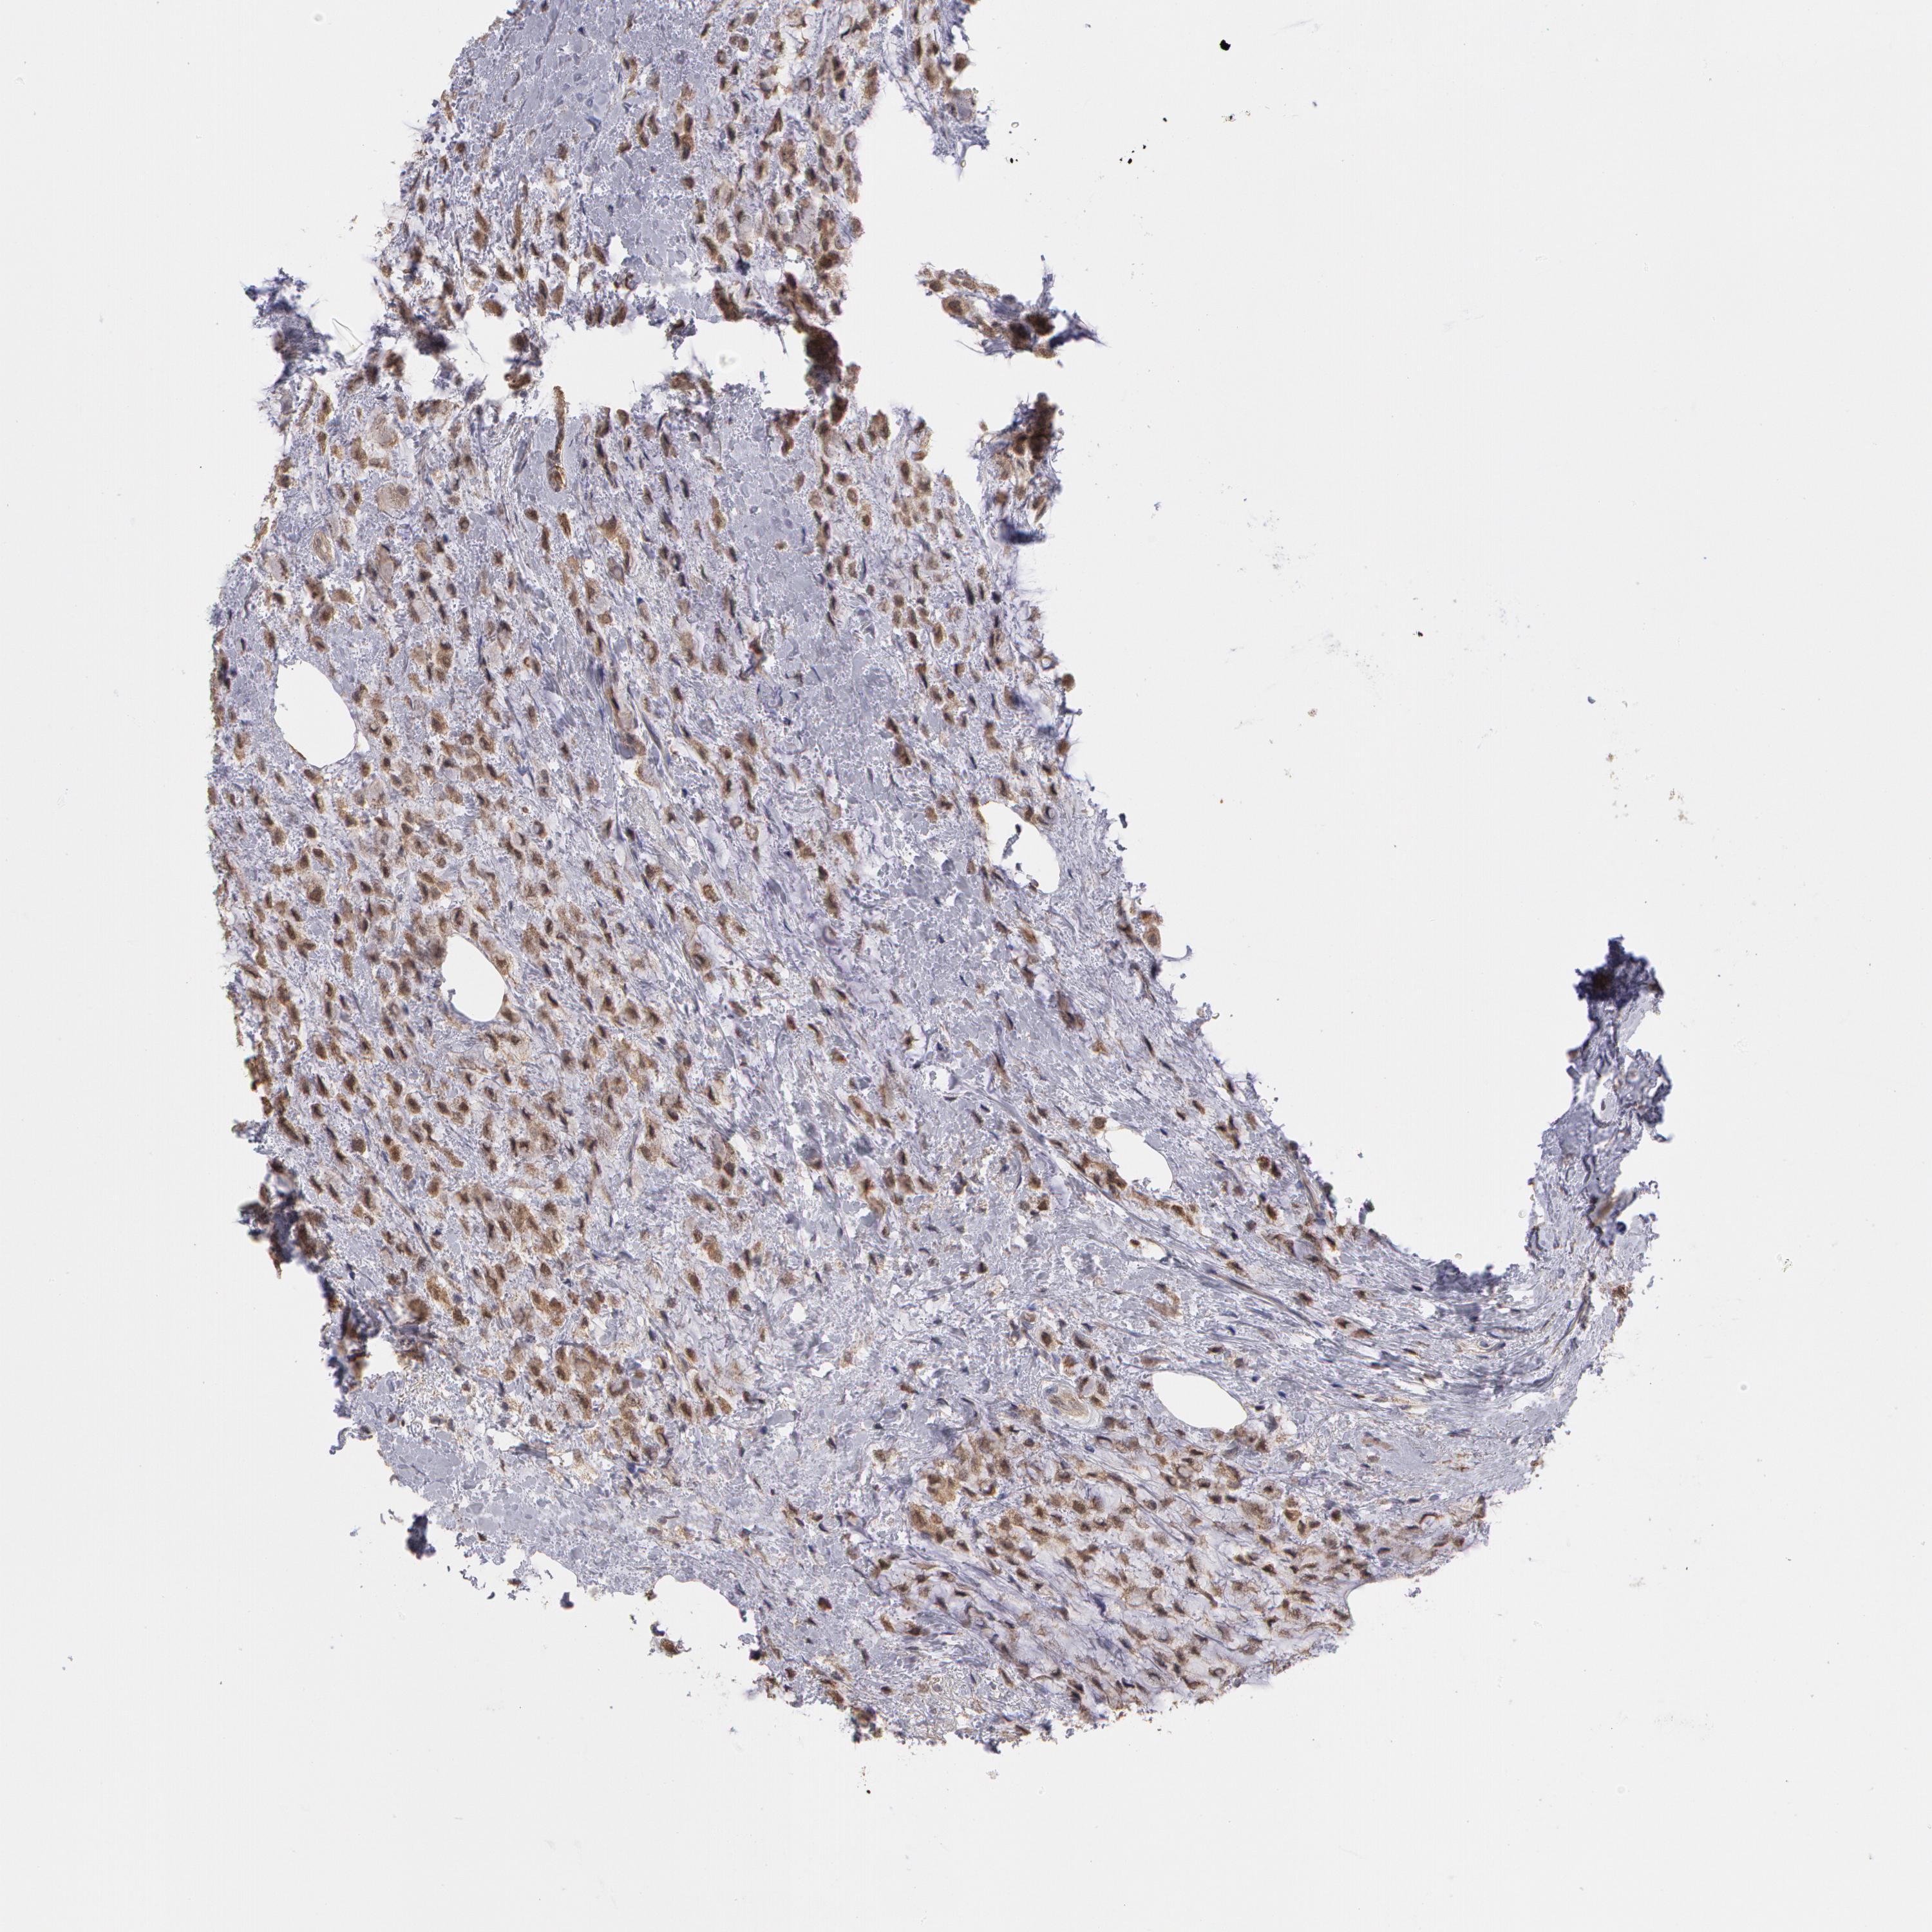

CANCER BREAST CANCER Show tissue menu

BRCA TCGA BRCA VALIDATION PROTEIN EXPRESSION

Breast cancer

Human cancer